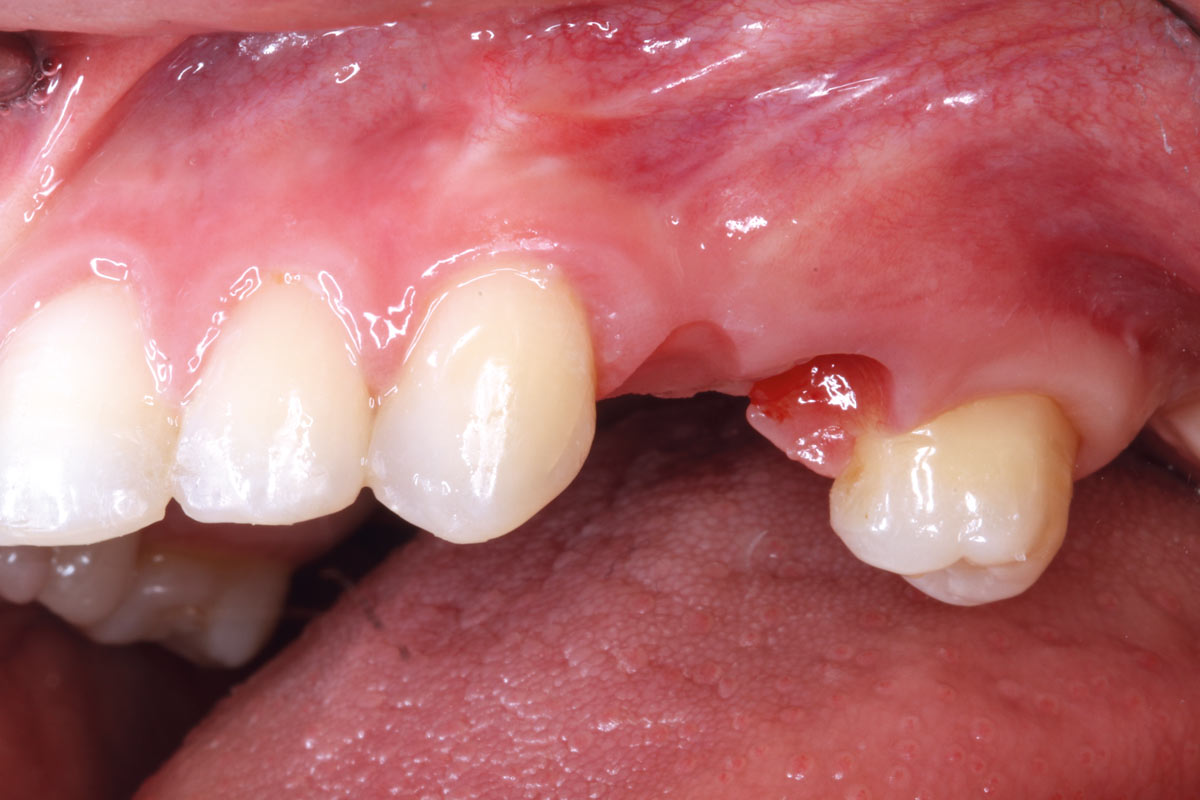

5/11 - Clinical situation after six months healingRidge reconstruction with maxgraft® block in the posterior maxilla - Dr. A. Puišys